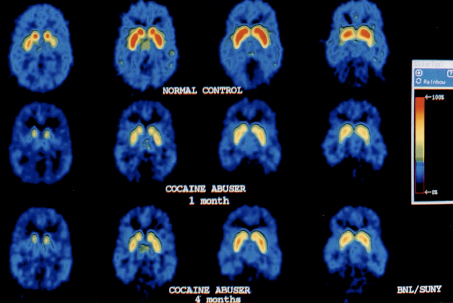

Long-term changes in the brain as a result of abuse

- Decreases in CREB transcription factor in NAc (and extended amygdala)

- Decreases in metabolism in orbito frontal cortex (OFC)

- Decreases in dopamine D2 receptor binding

Note: